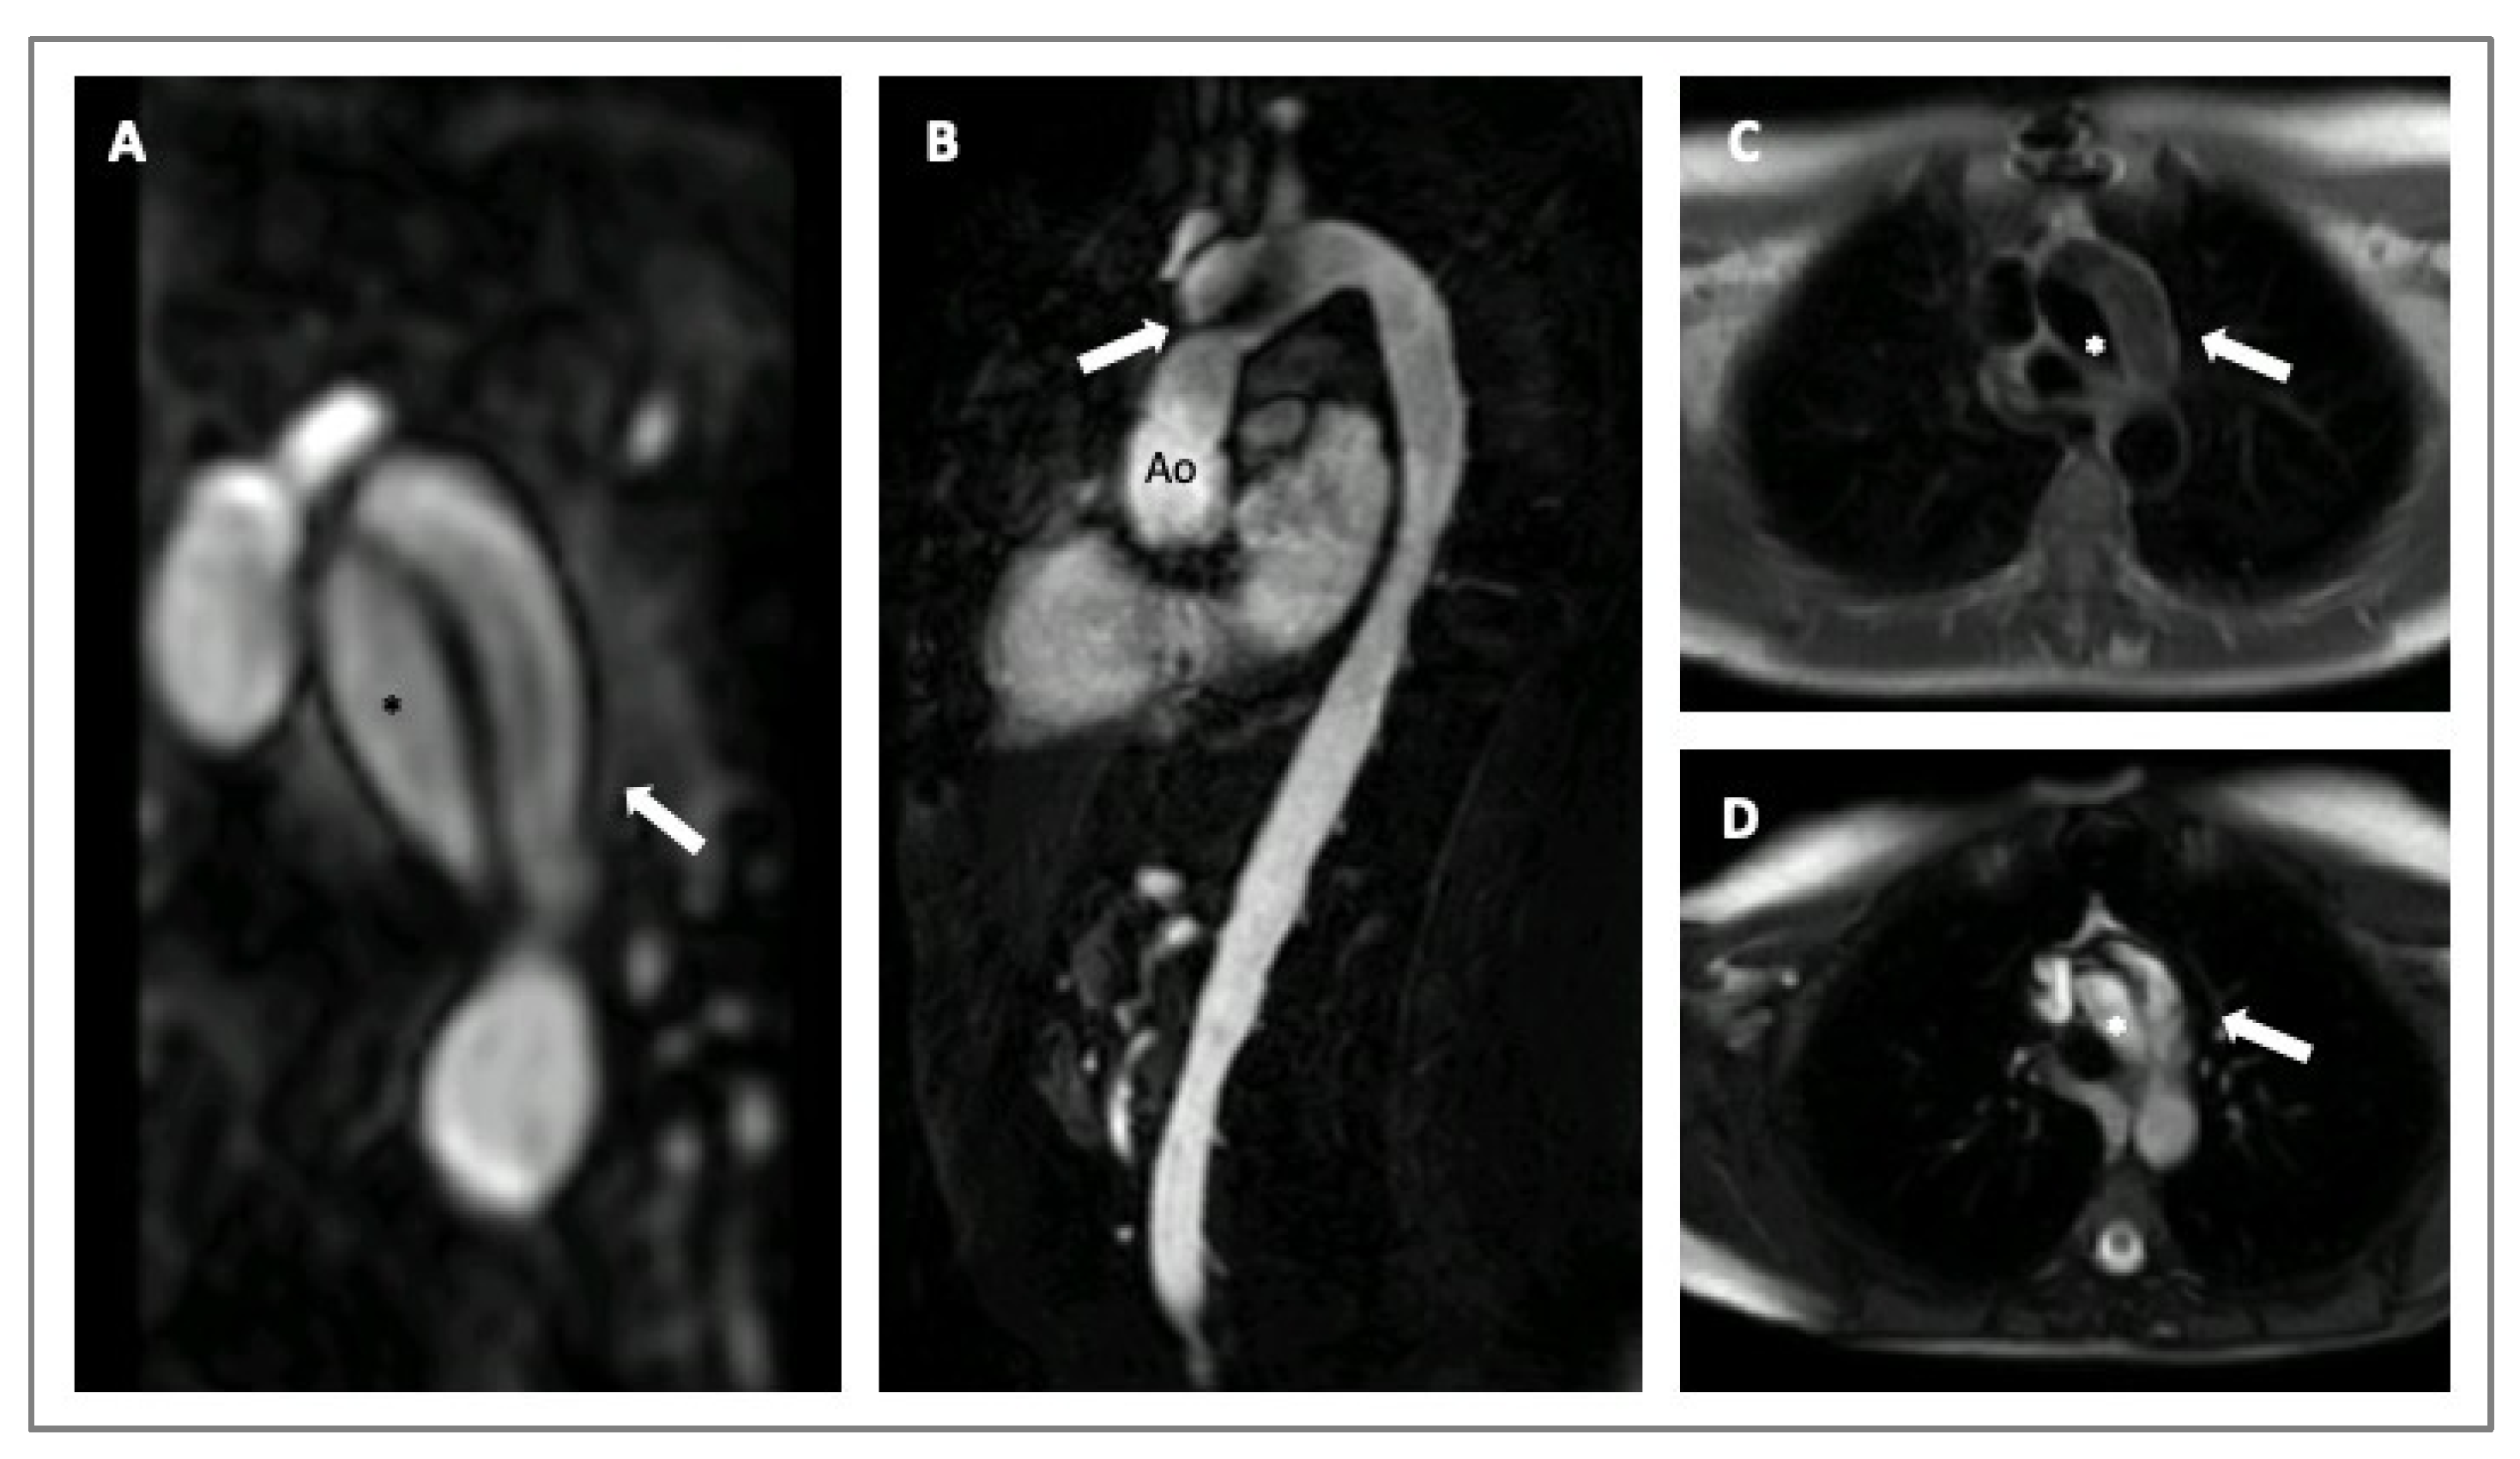

Cardiovascular magnetic resonance (CMR) is a valid imaging tool for aorta visualization that recently demonstrated good and consistent reproducibility in various contexts. CMR can acquire multiplanar and 3D cardiac and aortic images without using iodinate contrast agents and ionizing radiation at the expense of longer scan times. Furthermore, CMR can be considered the ultimate imaging technique for follow-up comparative studies, particularly on the young [32,33]. CMR also allows for evaluating aorta biomechanical parameters, such as stiffness, distensibility, and strain, used to assess aorta elasticity in patients with MS (Figure 4) [29,32]. Recently, 3D-cine (time-resolved) phase-contrast CMR with three-directional velocity encoding (4D flow) has been developed to study intravascular flow. It quantifies flow similarly to 2D-cine phase-contrast CMR, has good scan repeatability, and allows for analyzing wall shear stress or turbulent kinetic energy in patients with HTADs [29]. In fact, van Andel and colleagues recently demonstrated that abnormal aortic hemodynamics are associated with aortic complications in patients with MS, especially if patients are male and have a haplo-insufficient type of FBN1 mutation [34].

Figure 4.

CMR imaging of a 30-years old woman with MS presenting with an acute aortic dissection diagnosed during a routine exam. Angio-MRI with post contrast-enhanced sequence (Panel A); cine-SSFP sagittal and axial images (Panels B,D); T1-weighted axial images (Panel C). The asterisks indicate the true lumen and the arrows the false lumen. Legends: aorta (Ao); steady-state free precession (SSFP).